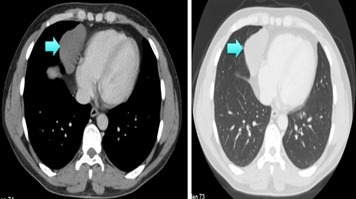

A 36-year-old male patient applied to an external center due to an upper respiratory tract infection that started about 4 months ago. Upon detection of a cystic lesion in the right paracardiac area, the patient was referred to our clinic (Figure 1). No abnormal findings were found in the physical examination, his cardiac rhythm biochemistry and blood test results were within normal limits. Thoracic computed tomography (CT) was performed on the patient. On CT, a cystic lesion of 7x4x5 cm with fluid density was observed in the epicardial fat pad (Figure 2). An operation was planned for the diagnosis and treatment of the case. Total cyst excision was performed with right SIVATS and the cyst was removed intact (Figure 3). The chest tube of the patient, whose control PA chest radiographs revealed a re-expanded lung, was removed on the 2nd postoperative day. The patient, who did not develop complications, was discharged on the 3rd postoperative day with full recovery.

Figure 2 Thorax computed tomography image of pericardial cyst.